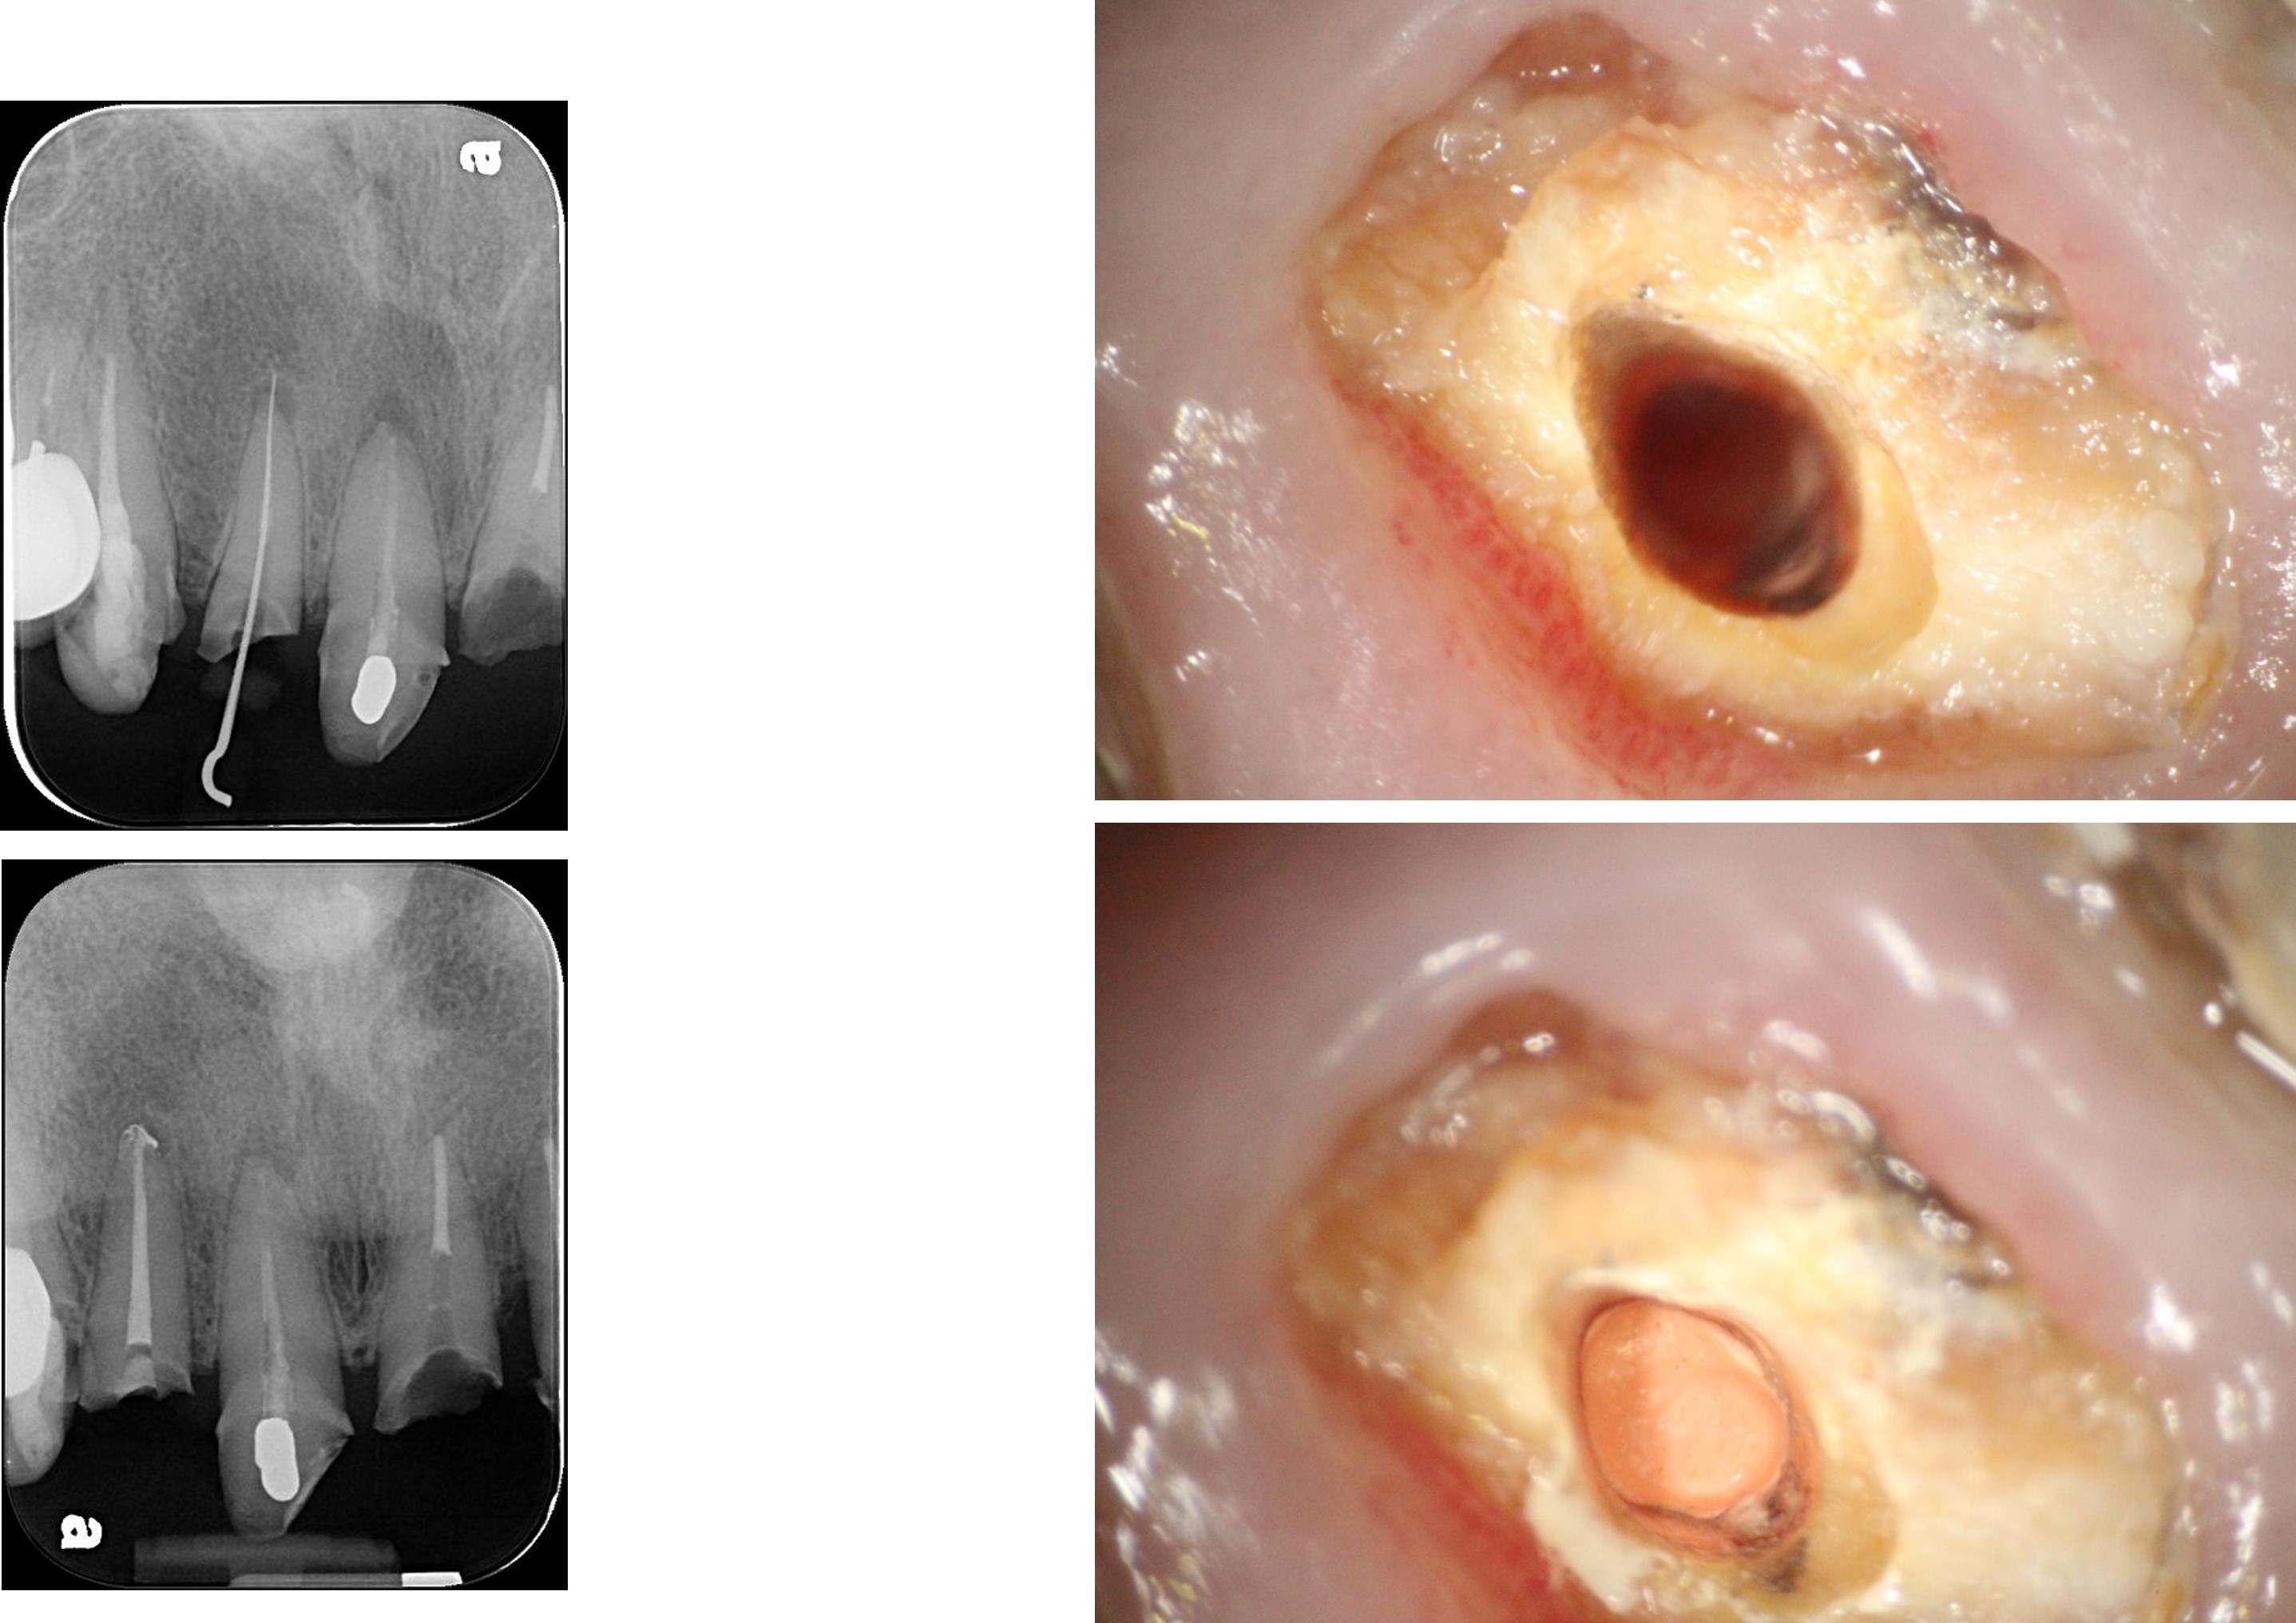

拔牙、立即植牙、補骨、補皮

牙齦豐隆度良好